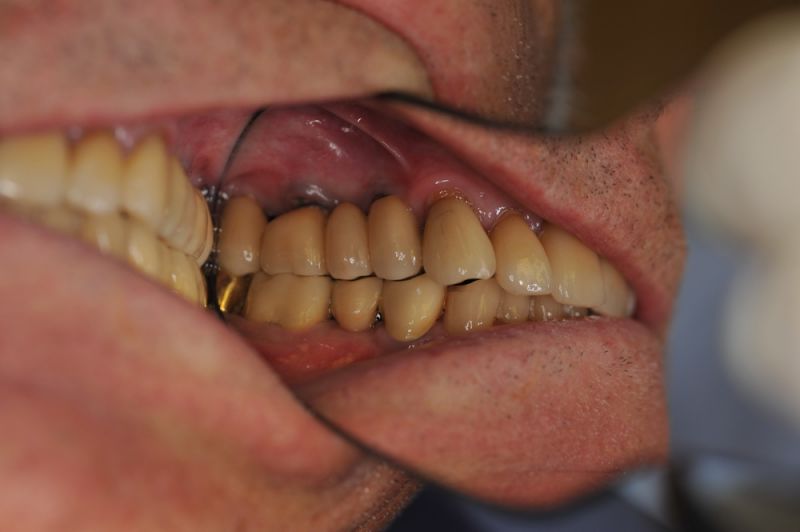

Die funktionstherapeutische Rekonstruktion befindet sich seit 17 Jahren im Munde des Patienten.

Gemeinsam ist man der Auffassung, dass sich heute zum Glück auszahlt, dass man beizeiten die Fundamente im Mund geschaffen hat, von denen der Patient heute im Alter zehrt.